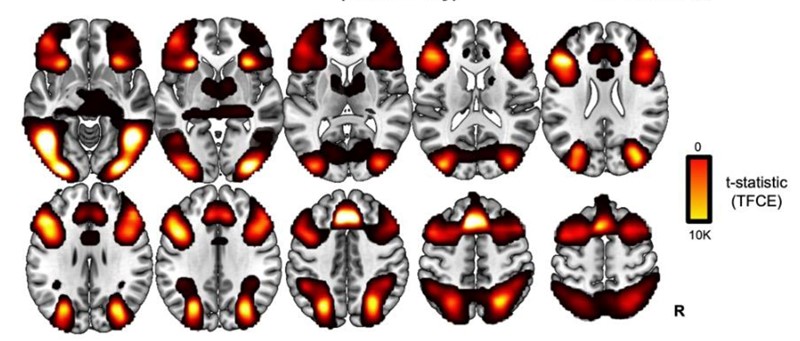

Studije oslikavanja mozga (neuroimaging) pokazale su da zadaci fluidne inteligencije uključuju i multiple demand network (MDN). Ova moždana mreža proteže se prednjim i stražnjim dijelom mozga, ali njezina aktivnost opada s godinama. To su pokazali i skenovi funkcionalne magnetske rezonancije (fMRI) kojim su znanstvenici istraživali obrasce moždane aktivnosti 223 odrasle osobe koje su rješavale zadatke različite težine.